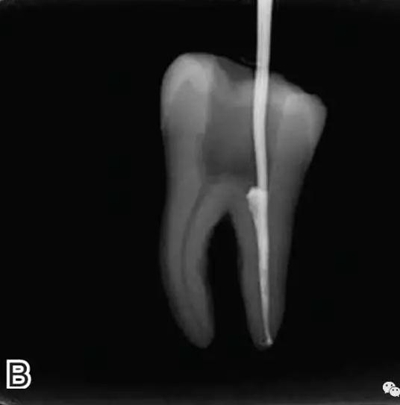

要求工作尖能自由到達(dá)距根尖4~5 mm(有學(xué)者提出3~4 mm)的位置并能輕微接觸根管壁,用橡皮片做好標(biāo)記(圖1)。

圖1 選擇攜熱器工作尖,A.試攜熱器尖 B.工作尖在根內(nèi)的位置